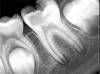

Fig 1. through Fig 3. Root filled with bioceramic sealer cut at different distances from the apex (Fig 1 through Fig 3: 0.5, 1.5, and 3.0 mm). One gutta-percha point is used as a plugger to move the sealer using hydraulic pressure. Note the irregularities are very well filled.

Pre-mixed BC Sealer is the only pure medical-grade bioceramic product available as a sealer for endodontic obturation. It has the same basic chemical composition as the other pre-mixed bioceramic products, but it is less viscous, which makes its consistency ideal for sealing root canals. It is used with a gutta-percha point, which is impregnated on the surface with a nano particle layer of bioceramic. The gutta-percha is used primarily as the delivery device (plugger) (Figure 1 through Figure 3) to allow hydraulic movement of the sealer into the irregularities of the root canal and accessory canals (Figure 4 and Figure 5).